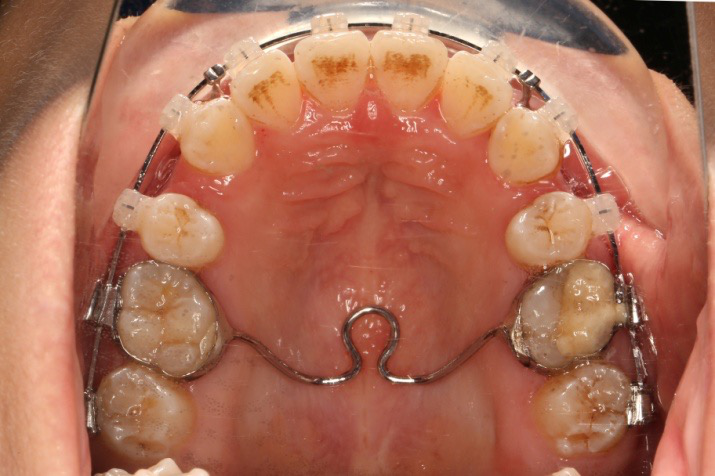

9.第20个月:2018.5.25 ◆ 拆tpa,16/26粘tube上和0.14*25cu-niti 下颌0.018*25niti

10.第22个月:2018.7.23 ◆ 上颌 0.010*25TMA,下颌0.017*25ss43压低曲,双侧后牙垂直牵引

11.第23个月:2018.09.29 ◆ 15/43/16/7/11/21重粘,上0.016*25cu-niti 下0.018niti 上连扎

12.第24.5个月:拆除矫治器,粘接上下舌侧保持器

2018.5.25  (19个月)拆TPA,16、26粘tube 上颌0.14*25cu-niti  下颌0.018*25niti2018.7.23  上颌 0.017*25TMA,下颌0.017*25ss43压低曲,双侧后牙垂直牵引

2018.09.29  15、43、16、17、11、21重粘,上0.016*25cu-niti 下0.018niti 上连扎